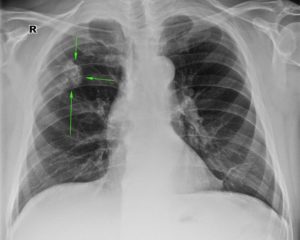

Как очаги в легких выглядят на снимке КТ?

Чтобы человек несведущий смог разобраться в результатах КТ, следует знать о нюансах чтения снимков. Рассмотрим самые актуальные:

- Очаговые образования представляют собой участки белого цвета на черном фоне (на снимке-негативе). В реальности пораженная область, скорее всего, имеет более темный цвет, чем здоровые ткани легкого.

- Если врач заметит на снимке участки кальцинирования или обызвествления (капсул, пропитанных солями кальция) вокруг очага, это может быть признаком доброкачественности образования. Кальцинаты по цвету похожи на кости скелета, видимые на этом снимке. Такие явления часто обнаруживаются после затяжных простудных заболеваний, бронхитов или уже излечененного туберкулеза и представляют собой некий шрам на легких. Пациента с образованием, на котором заметны признаки кальцината, пульмонологи обычно просят раз в полгода делать контрольные снимки.

- В случае, когда образование представляет собой так называемое «облачко» или очаг по типу «матового стекла», требуется более предметное обследование. Внешне оно выглядит как затуманенная область с размытыми границами. В ряде стран пациентам с такими образованиями сразу рекомендуется операция, даже если оно не растет. Уже доказано, что в 80% случаев такие очаги являются предраковым состоянием легких. Альтернатива немедленной операции — постоянное наблюдение с контрольными снимками раз в полгода-год.